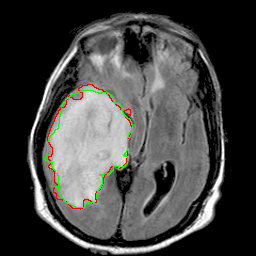

Loads a U-Net model pre-trained for abnormality segmentation on a dataset of brain MRI volumes kaggle.com/mateuszbuda/lgg-mri-segmentation The pre-trained model requires 3 input channels, 1 output channel, and 32 features in the first layer.

This U-Net model comprises four levels of blocks containing two convolutional layers with batch normalization and ReLU activation function, and one max pooling layer in the encoding part and up-convolutional layers instead in the decoding part. The number of convolutional filters in each block is 32, 64, 128, and 256. The bottleneck layer has 512 convolutional filters. From the encoding layers, skip connections are used to the corresponding layers in the decoding part. Input image is a 3-channel brain MRI slice from pre-contrast, FLAIR, and post-contrast sequences, respectively. Output is a one-channel probability map of abnormality regions with the same size as the input image. It can be transformed to a binary segmentation mask by thresholding as shown in the example below.

Input images for pre-trained model should have 3 channels and be resized to 256×256 pixels and z-score normalized per volume.